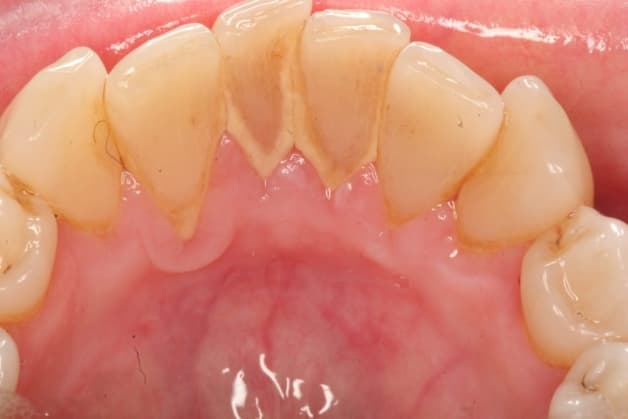

Vôi răng tạo nên từ vi khuẩn tác động lên các thức ăn còn sót lại

Cao răng còn được gọi với tên là vôi răng. Đó là những mảng bám cứng và dính chặt với bề mặt răng. Cao răng hình thành bởi các vi khuẩn tác động lên những thức ăn còn sót lại. Lâu ngày, chúng sẽ tích tụ, cứng dần và bám chặt ở ngay đường nướu hay dưới đường nướu. Tình trạng này có thể gây sự kích ứng mô nướu.

Dấu hiệu nhận biết dễ nhất của tình trạng cao răng là một lớp có màu vàng hoặc màu nâu ở trên nướu. Tình trạng này gây ảnh hưởng tương đối tới tính thẩm mỹ.